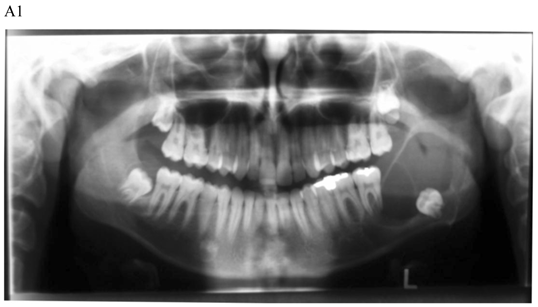

For most of the cysts, plain film radiography (PFR) was an adequate imaging modality. In some of the cases, CT with MPR program was also performed. The CT with MPR software, originally designed for implant dentistry, has proven to be useful in the evaluation of jaw abnormality and pathology [4, 15-19]. Using this software program, anatomic structures, such as the mandibular canal, mental foramen, incisive canal, and maxillary sinus, can be seen in cross-section. CT with MPR has also been shown to be superior to PFR in demonstrating cystic lesions of the jaws and in evaluating bone regeneration following marsupialization of jaw cysts [17-19].

The main advantage of CT with MPR is that it allows planning of the surgical approach with the least morbidity to the adjacent anatomic structures [20]. Despite the advantages, CT should not be used routinely, but rather reserved for large lesions, particularly those where extension into the nasal cavity, maxillary antrum, orbit, or pterygomaxillary space must be assessed.

The treatment objective is restoring the morphology and function of the affected area. There are two basic surgical procedures, namely marsupialization (decompression) (Fig.1) and enucleation. Marsupialization, a relatively simple procedure, consists of surgically producing a “window” in the cystic wall to relieve intra-cystic tension. After this, the cystic cavity slowly decreases in size. The cavity is lightly packed with paraffin gauze until the line of junction between the cystic lining and the oral mucosa has healed. Three to six months later, enucleation is performed [16].

Figure 1

Dentigerous cyst affecting the left mandible of a 15-year-old boy treated by marsupiallization. At presentation, there was an acute infection in the area. A) Pre-operative radiographs: 1) Panoramic radiograph demonstrating a tooth within a large radiolucent area in the left mandible; 2) Axial CT scan demonstrating expansion of the body of the left mandible with very thin buccal and lingual cortices. A tooth is within the lumen; 3) Coronal CT of the mandible demonstrates an expansion of the ascending ramus of the left mandible with very thin cortical borders. A tooth is within the lumen. B. Postoperative radiographs: 1) Panoramic radiograph shortly post-marsupialization, extraction of tooth 37 that was adjacent the cyst as well as tooth 38 that was within the cyst; 2) Panoramic radiograph one year post-treatment. The radiodensity of the cystic area is similar to normal bone, indicating complete bone regeneration.

Enucleation with primary closure is the treatment of choice [22]. It is a one-stage surgical treatment followed by periodic radiographic examinations at regular intervals to observe the progress of bone regeneration of the defect. It also allows pathologic examination of the entire specimen for histopathologic diagnosis. Enucleation can be done only when the jaw bone adjacent to the cyst is intact. If CT demonstrates erosions in the buccal or lingual cortices, marsupialization should be the treatment of choice (Fig. 1) [4].